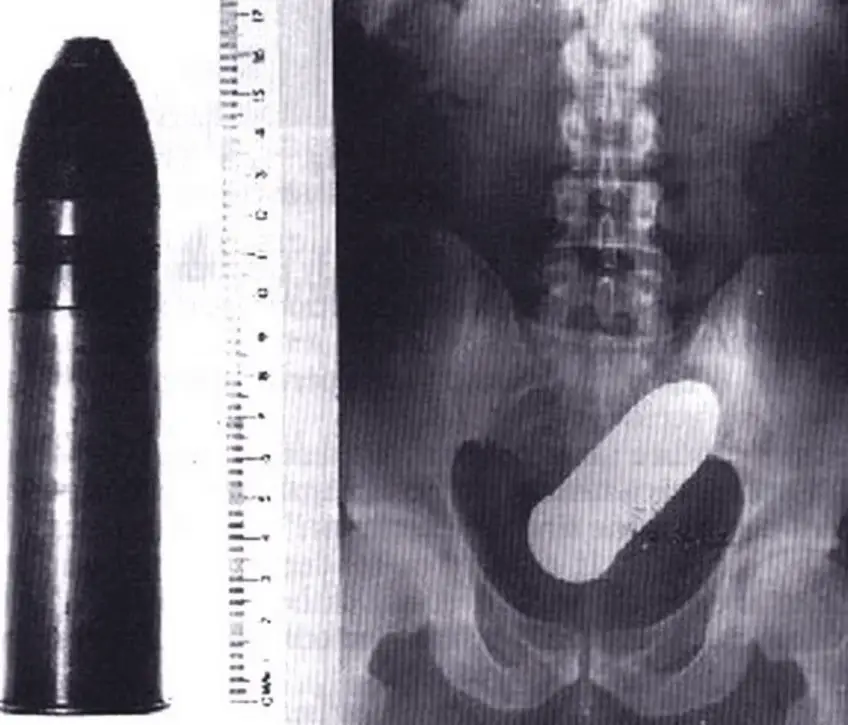

MEDICINA ONLINE OGGETTI CORPO ESTRENEO ANO BAMBINO ESOFAGO STOMACO BATTERIE SEX TOYS OGGETTI SESSO GIOCATTOLI TOSSICI BOTTIGLIA PENNA PENNARELLO COLON RETTO RISCHI COSA FARE COLONSCOPIA

Published 18/04/2018 at 1118 × 956 in Corpi estranei nel tratto digerente: rischi e cosa fare in bambini e adulti

MEDICINA ONLINE OGGETTI CORPO ESTRENEO ANO BAMBINO ESOFAGO STOMACO BATTERIE SEX TOYS OGGETTI SESSO GIOCATTOLI TOSSICI BOTTIGLIA PENNA PENNARELLO COLON RETTO RISCHI COSA FARE COLONSCOPIA INTESTINO DIGERENTE RX RADIOGRAFIA